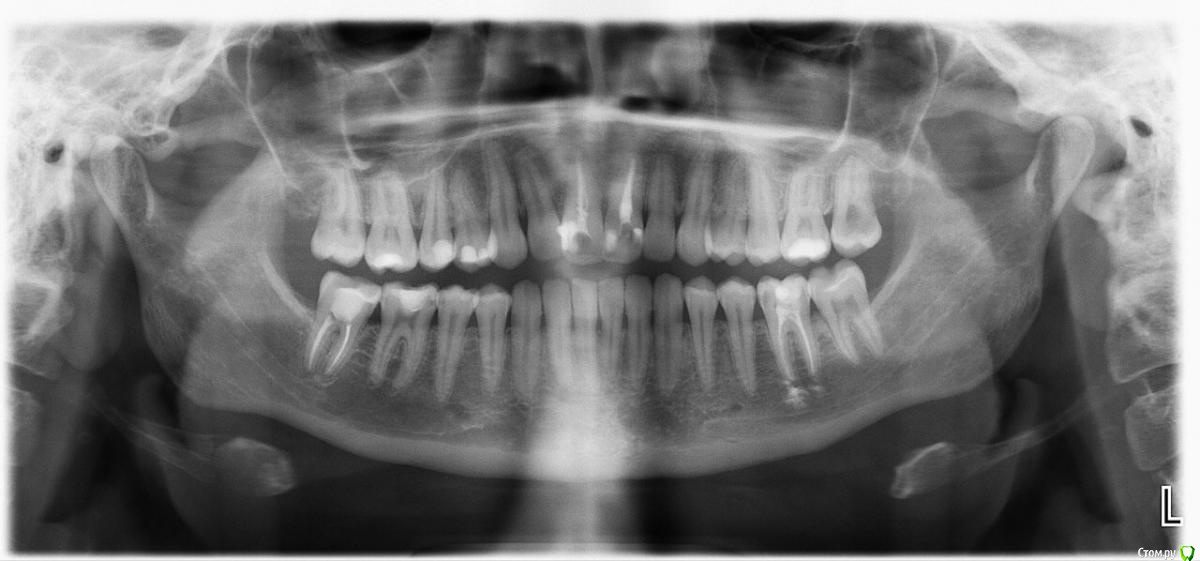

Буду благодарна если поможете разобраться. Три месяца назад заболел зуб. При обращении в стоматологию выяснилось, что у меня периодонтит двух передних зубов, оба зуба были пролечены. Прошло практически два месяца оба зуба все равно болят, один просто ноющей болью постоянно, другой при надкусывании. Оба зуба подвижны. При повторном обращении был сделан панорамный снимок, на котором нет следов воспаления, но врач отметил, что лунка каждого зуба в челюсти больше чем положено и он не понимает с чем это связанно. При первом обращении я отметила, что присутствует не сильная, ноющая боль как будто во всех зубах ( не понять какой именно зуб болит) в нижней челюсти. По факту у меня сейчас болят чуть ли не все зубы, а в чем дело не ясно. Мне 30 лет, год на гв. До назначенного приёма ещё две недели . Не знаю как спасаться. Заранее спасибо!

На панорамном снимке периапикальная область центральных зубов замыливается, необходимо сделать прицельные снимки этих двух зубов и выложит их в тему.